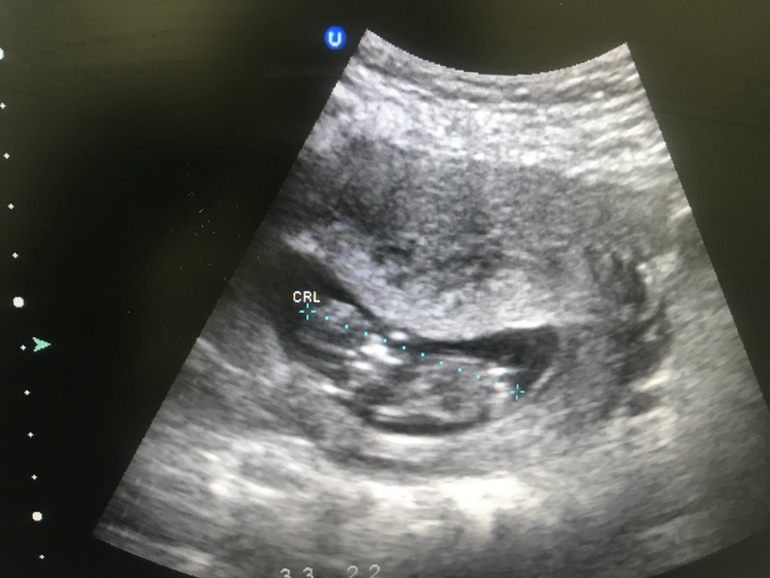

Вот сходила

Сегодня на узи , врач как я поняла пол не могла определить говорит не пойму рано ещё )